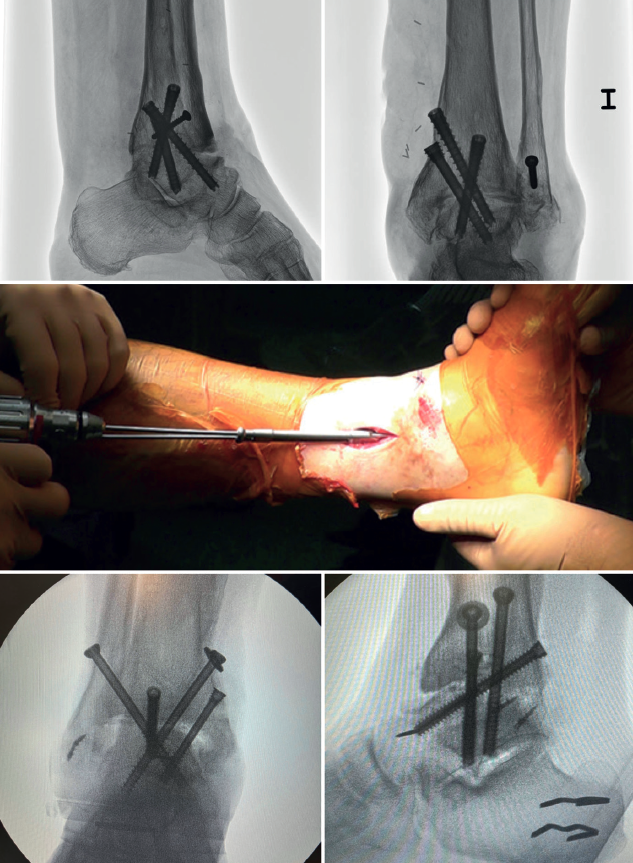

In arthroscopic ankle arthrodesis, the use of percutaneously placed compression screws is the technique of choice (Figure 5).

Most authors consider the use of cannulated screws (3 to 4) to be the ideal fixation method. The diameters of the chosen screws should be between 6 and 7 mm. This technique achieves 85-100% fusion and 84-95% patient satisfaction rates(19).

Screw configuration and placement

Depending on the deformity involved and according to preoperative planning, screw placement is carried out starting with the compression screw that counteracts the deformity.

In other words, in arthropathies with a varus component, we would start with a lateral screw, while in valgus misalignments the recommendation is to place the first screw from the medial side. The second screw should be on the side opposite to the first. Both should provide adequate compression between the joint surfaces(17).

In general, a minimum of three screws are used. The third screw is the so-called home run screw, the importance of which has been highlighted by Holt et al.(21). It is directed across the ankle from the posterior part of the tibia to the neck of the talus. A fourth screw may be used as an augmentation of the first, counteracting the main deformity.

Glick, Myerson(23) et al. reported that the configuration conferring the greatest rigidity to the osteosynthesis comprises two screws from medial and one from the lateral side.

Definitive anteroposterior, mortise, lateral ankle, dorsoplantar and oblique foot radiographs are obtained to confirm correct reduction, and the position and length of the screws, especially the home run screw (Table 3).